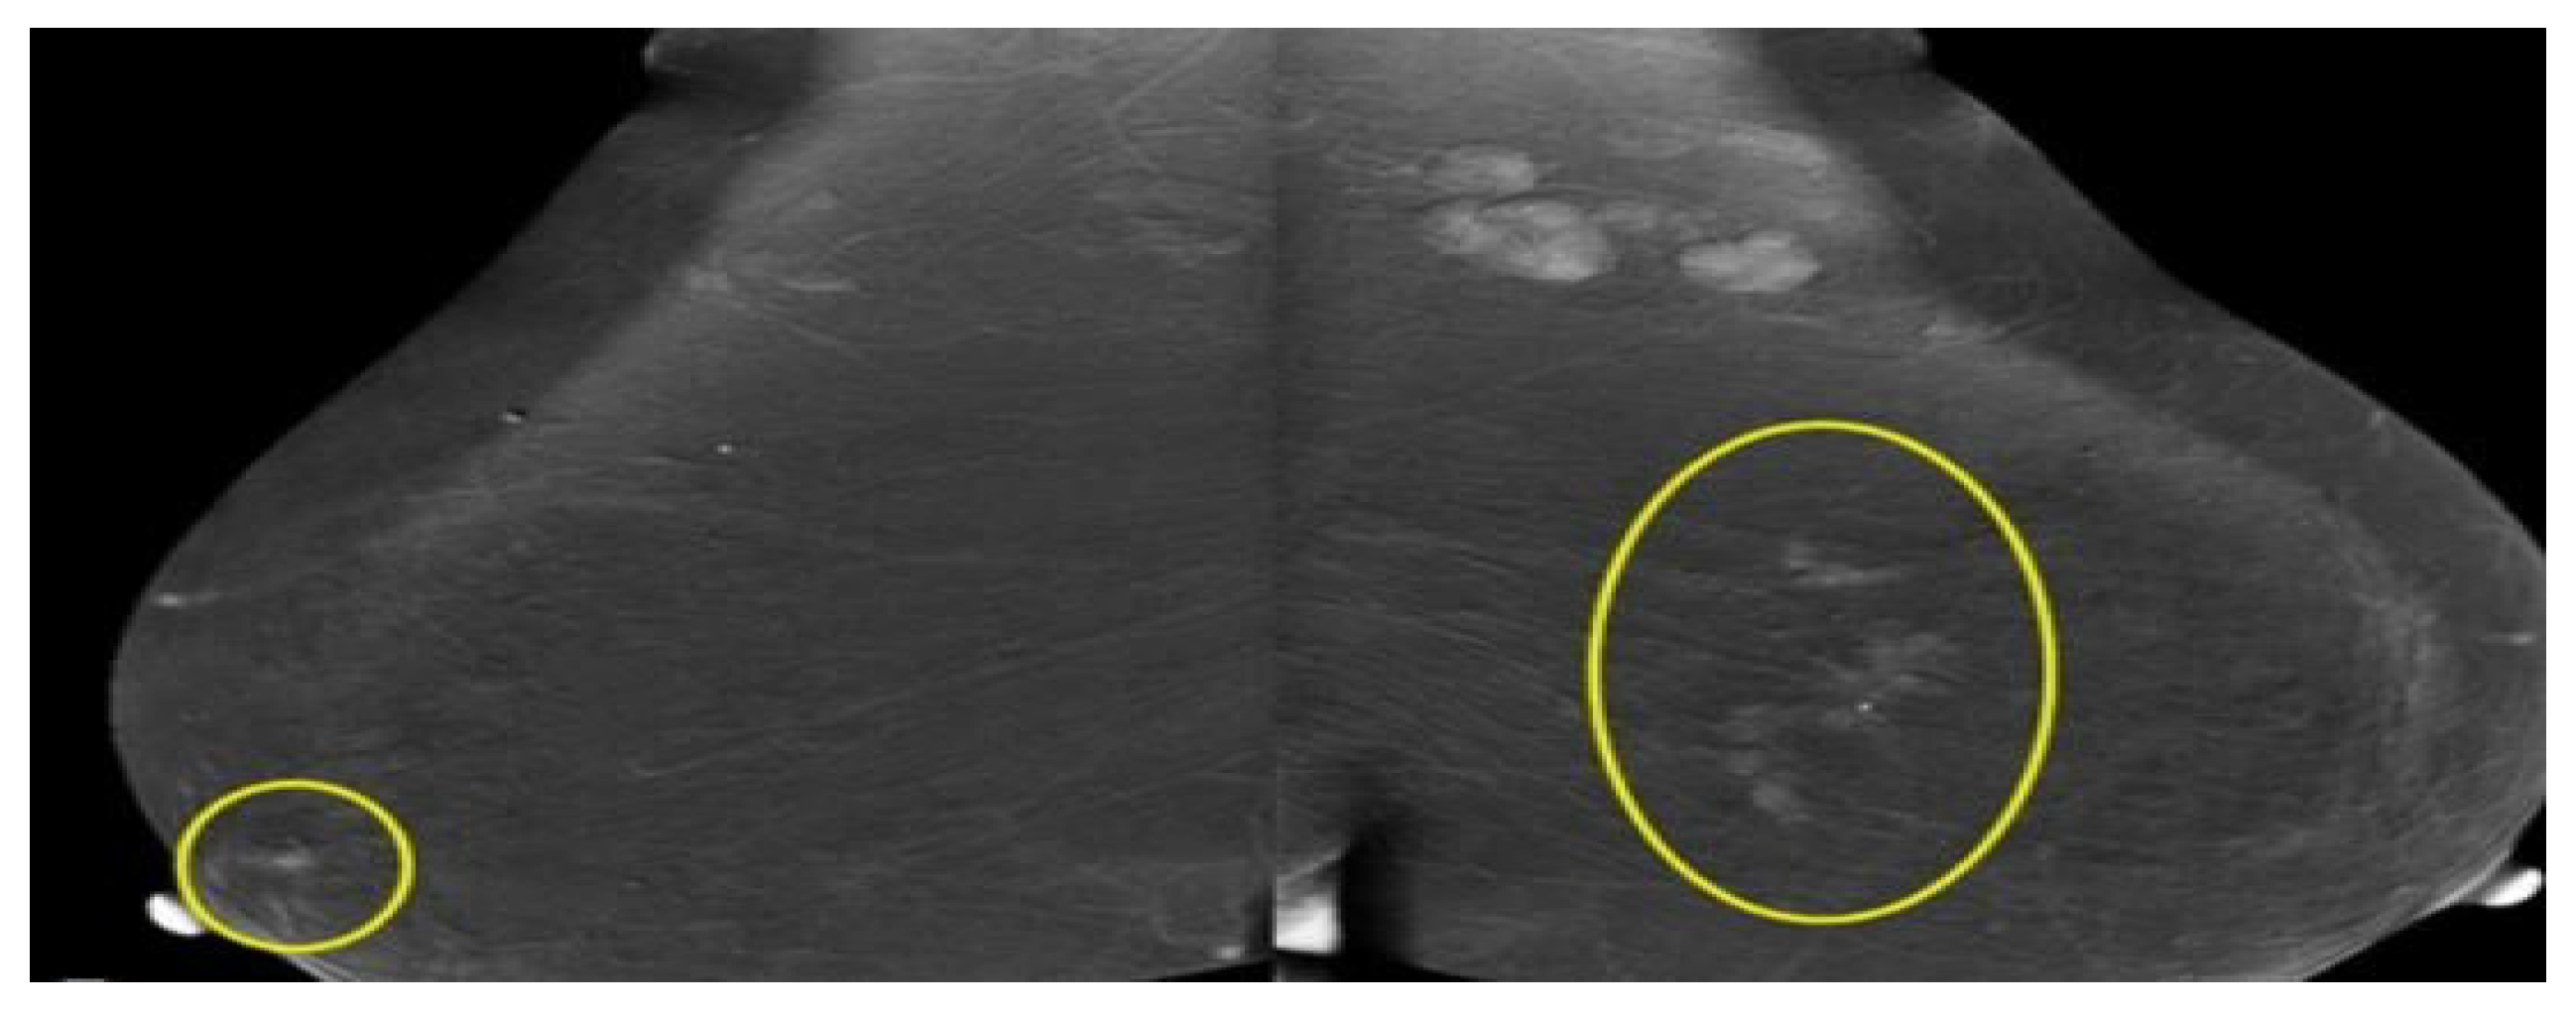

2.1.2. Mammography

- Emine, D.; Suzana, M.K.; Halit Ymeri, A.K. Comparative accuracy of mammography and ultrasound in women with breast symptoms according to age and breast density. Bosn. J. Basic Med. Sci. 2009, 57, 205–216. [Google Scholar] [CrossRef]

- Kamal, R.; Mansour, S.; Farouk, A. Contrast-enhanced mammography in comparison with dynamic contrast-enhanced MRI: Which modality is appropriate for whom? Egypt. J. Radiol. Nucl. Med. 2021, 52, 216. [Google Scholar] [CrossRef]